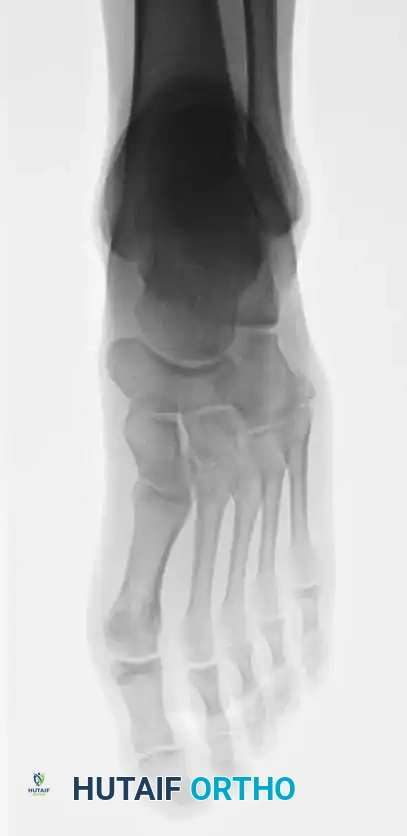

Fig. 86-44 A-C, Type IIIB (DeLee) fi fth metatarsal fracture.

Fig. 86-44 A-C. Preoperative radiographs of a Type IIIB (DeLee) fifth metatarsal fracture demonstrating significant intra-articular displacement requiring surgical reduction.